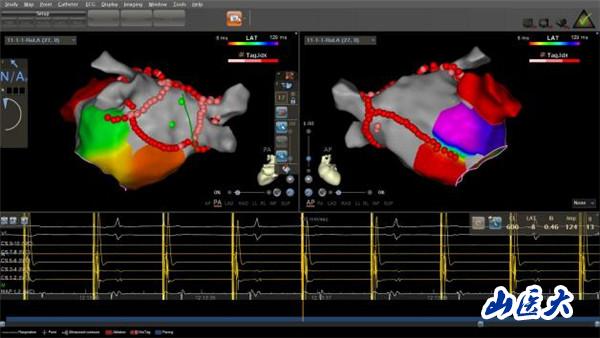

“射频消融术?就是那种有辐射的手术吗?”家属闻此顾虑重重,怕射线给老人的身体带来更大伤害。王睿主任医师解释说,在传统射频消融术中,X射线是实现手术可视化的必要条件,如果不借助X射线进行操作,之前射频消融术是无法实施的。随着医学技术的发展,目前采用CARTO(三维电解剖标测系统)开展零X射线下射频消融术,就像给医生安了一双“慧眼”,无须在X射线透视下,即可实现精准导航。这种新技术,在手术过程中放置标测电极和操作消融大头电极等均采用三维电生理标测系统指导,完全不用X射线透视,却对手术医生技术的熟练程度、导管的操作技术以及心脏解剖三维理解要求极高。通过该技术既能获得准确靶点,缩短手术时间,提升手术安全性,让患者避免了X线辐射,也让医生避免了披“甲”上阵、负重手术,因此被称为绿色电生理射频消融术。

经过充分沟通,由王睿主任医师率领的心电生理团队在CART0指引下,十分精准地操控导管在患者心脏内走行、检查、建立模型、精准定位、消融靶点。术中,老人生命体征平稳,无明显不适。三个小时后,手术顺利完成,老人心脏恢复窦性心律,长期困扰其的房颤终于“驱魔”成功。

值得一提的是,当天除了该房颤患者外,还为两位阵发性室上速患者完成了绿色电生理射频消融术,即一天内顺利完成3例零射线射频消融手术,山西省尚属首次。近半个月的时间,电生理团队已经为二十余名患者进行了零射线射频消融,疾病涉及室上速、房速、房扑、房颤、室早等各种心律失常,其中还有一名怀孕5个月的孕妇。